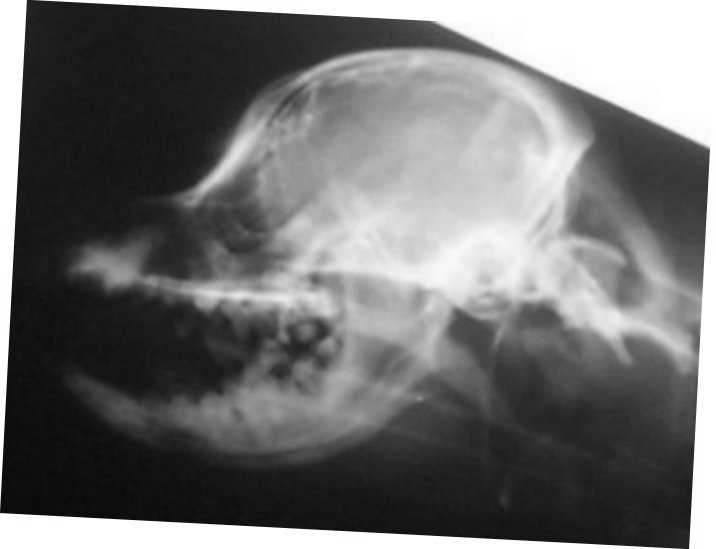

amount of CM. Here is a comparison of two skull x-rays which

show why this particular measurement indicates amount of CM. The

top one is a skull x-ray of a Cavalier with severe CM (and has

SM as well) and the bottom one is a skull x-ray of a Cavalier

with very little to no CM (and no SM).

The line was drawn from right in front of the 'hole'

(black spot), center of that curved bone (the 'jaw hinge' area)

to where the most thickened area of the skull ends (and the

occipital area begins). In the dog with almost no CM and no SM

you can CLEARLY see there is a lot more lower backskull left

behind/below that line as compared to the dog above--which

literally has almost none! This also happens to be the area

where the cerebellum sits so it would be common sense that the

dog in the top x-ray would have much less room for the

cerebellum than the dog on the bottom--and therefore more CM (chiari

malformation). There just isn't any skull left for there to be

enough room for the cerebellum. It appears here that a good

skull x-ray may be very useful in determining amount of CM and

therefore breeding towards a goal of less and less CM in future

offspring and thereby lessening the prevalence of SM. A skull

x-ray is much cheaper than an MRI which will enable many more

breeders to x-ray for amount of CM in the future as more

information becomes available.